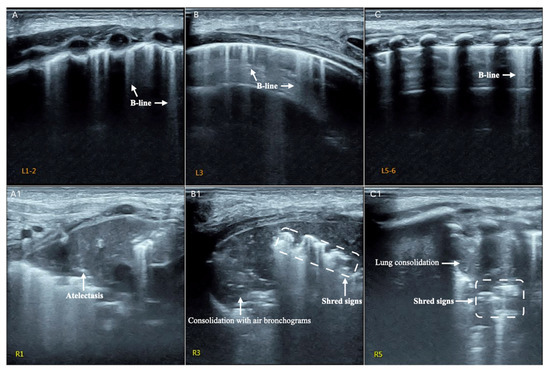

| Definition | |

|---|---|

| Consolidation | Area in which lung tissue is de-aerated with density similar to parenchymal tissues [23] |

| Atelectasis | Type of consolidation shown as hyperechogenic tissue structure visualized as solid parenchyma with static air bronchogram [11,24] |

| Cavitation | Solid, hypoechoic, heterogeneous lesions with sharp lobulated margins [11,25] |

| Pleural effusion | Hypo- or anechogenic structure, delineated by the chest wall and the diaphragm [11,26] |

| B-lines | Vertical reverberation artefacts from the pleural line to the edge of the scree; laserlike, vertical hyperechogenic artefacts synchronized with pleural line [11,23,27] |

| Pleural irregularities | Reduction or interruption of pleural line [11,28] |

| Sub-pleural nodes/granularities | Hyperechogenic subcentimetric granularities or consolidation under the pleural line [29,30] |

| N. of Patients | Mean Age | Pleural Effusion | Pleural Irregularities | Consolidation | Cavitation | Subpleural Nodes | Subpleural Granularities | B-Lines | |

|---|---|---|---|---|---|---|---|---|---|

| Children | |||||||||

| Heuvelings, 2019 [42] | 40 | 2 yrs | 12 (30%) | 31 | 22 | 0 | 0 | 0 | 13 |

| (78%) | (55%) | (33%) | |||||||

| Adults | |||||||||

| Hunter, 2016 [30] * | 10 | 33 yrs median | 0 | 0 | 0 | 0 | 0 | 10 | 10 |

| (100%) | (100%) | ||||||||

| Agostinis, 2017 [29] | 60 | 32 yrs | 11 | NS | 28 | 3 | 58 | 4 | NS |

| (18%) | (46%) | (5%) | (98%) | (6%) | |||||

| Montuori, 2019 [43] | 51 | 34 yrs | 10 | 37 | 40 | 9 | 37 | 0 | 0 |

| (20%) | (73%) | (77%) | (30%) | (73%) | |||||

| Fentress, 2020 [44] | 51 | 34 yrs | 4 | NS | 41 | 3 | 41 | 0 | 20 |

| (7%) | (80%) | (6%) | (80%) | (39%) | |||||

| Cocco, 2022 [45] | 1 | 36 yrs | 1 (100%) | 0 | 1 | 1 | 0 | 0 | 0 |

| Total (adults) | 173 | 26 | 37 | 110 | 16 | 136 | 14 | 30 | |

| (15%) | (59%) | (63%) | (9%) | (78%) | (8%) | (26%) | |||